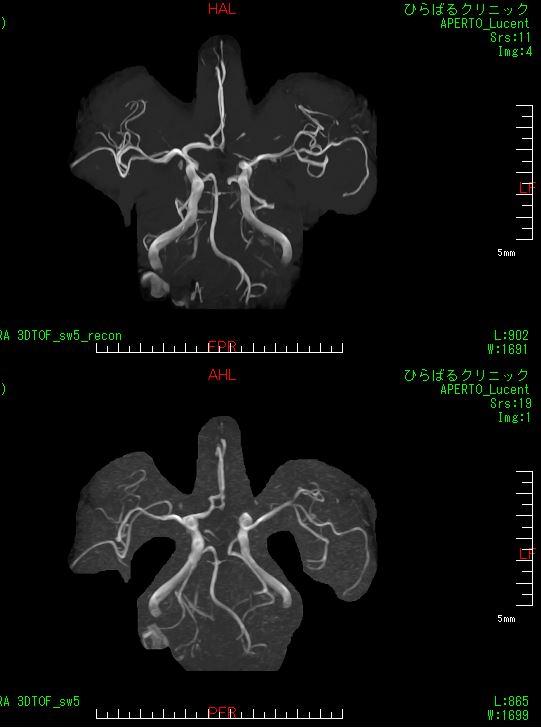

下記に処理前後の画像を提示します。同業者の方は驚嘆するのではないでしょうか。上が処理後、下が処理前になります。

(画像は院長の頭部です)